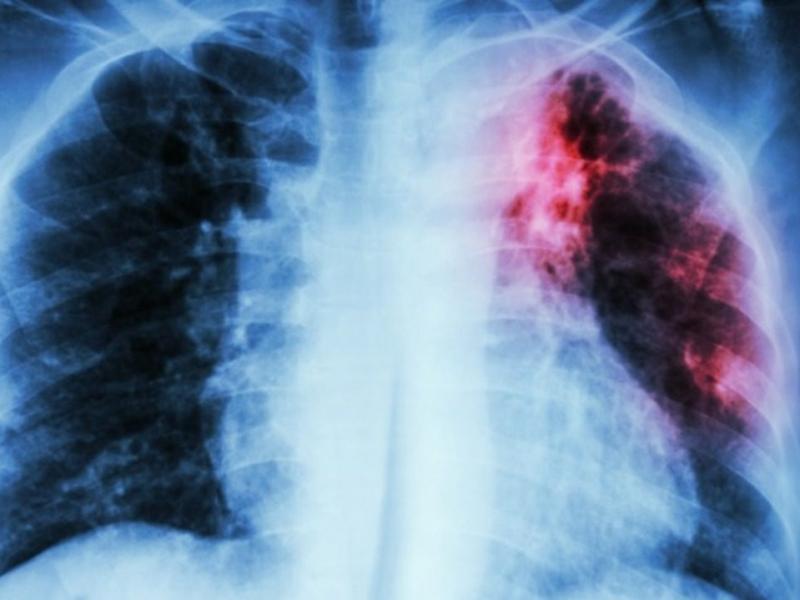

Η φυματίωση δεν μας ξεχνά, είναι εδώ. Πρόκειται για μείζον πρόβλημα που εξακολουθεί να απειλεί τη δημόσια υγεία με ορατό κίνδυνο περαιτέρω όξυνσής του τα επόμενα χρόνια, ανέφεραν κατά τη διάρκεια συνέντευξης Τύπου, οι εκπρόσωποι της Ελληνικής Πνευμονολογικής Εταιρίας (ΕΠΕ), με αφορμή το 28ο Πανελλήνιο Πνευμονολογικό Συνέδριο, 12-15 Δεκεμβρίου, στην Αθήνα.

Κυριότερο εμπόδιο για τον έλεγχο της αποτελεί η έλλειψη Εθνικού Προγράμματος για τη Φυματίωση, υπογράμμισε ο Χαράλαμπος Μόσχος, πνευμονολόγος-φυματιολόγος, ταμίας της ΕΠΕ, προσθέτοντας ότι η ύπαρξή του αποτελεί απαραίτητη προϋπόθεση για την εξασφάλιση του συντονισμού όλων των απαιτούμενων δράσεων για την αντιμετώπιση και τον έλεγχο του νοσήματος, στους τομείς του προσυμπτωματικού ελέγχου, της διάγνωσης, της θεραπείας και του ελέγχου των στενών επαφών στο περιβάλλον των πασχόντων και της επιτήρησης του νοσήματος. Η έλλειψή του, είπε, οδηγεί σε πλήρη σύγχυση στόχων και αδυναμία συντονισμού της προσπάθειας για την αντιμετώπιση του προβλήματος. Η φυματίωση αποτελεί νόσημα που πλήττει περισσότερο τις ευπαθέστερες ομάδες πληθυσμού και συγκεκριμένα πρόσφυγες και μετανάστες, ηλικιωμένους, κρατούμενους, χρήστες παράνομων ουσιών, ασθενείς με HIV λοίμωξη και άλλα αίτια ανοσοκαταστολής.

Ο κ. Μόσχος ανέφερε, ότι στην Ελλάδα, ο προσυμπτωματικός έλεγχος για φυματίωση ευάλωτων ομάδων είναι, στην καλύτερη περίπτωση, «αποσπασματικός, ανεπαρκής και ελλιπώς σχεδιασμένος. Το αποτέλεσμα είναι οι περισσότεροι ασθενείς να διαγιγνώσκονται με σημαντική καθυστέρηση, με εκτεταμένη φυματίωση και έχοντας ήδη διασπείρει τη νόσο σε βαθμό που ο περιορισμός της να μην είναι εφικτός, ενώ άγνωστος αριθμός ασθενών να παραμένει χωρίς διάγνωση και θεραπεία».

Στην Ελλάδα, με βάση τα επιδημιολογικά δεδομένα του ΕΟΔΥ, το 2018 δηλώθηκαν 432 νέες περιπτώσεις φυματίωσης. «Δυστυχώς, στη χώρα μας παρατηρείται διαχρονικά σοβαρή υποδήλωση του νοσήματος. Με βάση τα αποτελέσματα επιστημονικών μελετών, η πραγματική επίπτωση της φυματίωσης στην Ελλάδα υπολογίζεται τουλάχιστον τριπλάσια έως πενταπλάσια της δηλούμενης. Ταυτόχρονα, παρατηρείται μια μικρή διαχρονική αύξηση των περιστατικών πολυανθεκτικής φυματίωσης», ανέφεραν οι εκπρόσωποι της ΕΠΕ. Σύμφωνα με τους επιστήμονες, σημαντικό πρόβλημα στην αντιμετώπιση και τον έλεγχο της φυματίωσης στη χώρα μας αποτελεί επίσης η απουσία κατάλληλων συνθηκών νοσηλείας, οι σοβαρές ελλείψεις και καθυστερήσεις στην προμήθεια των αντιφυματικών φαρμάκων, ιδίως των νεότερων, με αποτέλεσμα επικίνδυνες καθυστερήσεις στην έναρξη και διακοπές της αντιφυματικής θεραπείας, που θέτουν σε σοβαρό κίνδυνο ασθενείς και προσωπικό. Επίσης, σημαντικός αριθμός ασθενών με ενεργό φυματίωση που ξεκινούν αντιφυματική αγωγή διακόπτουν από μόνοι τους τη θεραπεία και χάνονται από την παρακολούθηση, με κίνδυνο δημιουργίας και διασποράς ανθεκτικών στελεχών στην κοινότητα, ενώ απουσιάζουν πλήρως προγράμματα άμεσα εποπτευόμενης θεραπείας (DOT), με στόχο τη βελτίωση της συμμόρφωσης ευάλωτων ομάδων ασθενών στην αντιφυματική θεραπεία.

Παγκοσμίως υπολογίζεται ότι περίπου 2 δισεκατομμύρια άνθρωποι, δηλαδή το 1/3 του παγκόσμιου πληθυσμού, έχουν σε κάποια στιγμή της ζωής τους μολυνθεί από το μυκοβακτηρίδιο της φυματίωσης. Παρότι η συντριπτική πλειονότητα, -το 90%- αυτών δεν πρόκειται ποτέ να αναπτύξει ενεργό νόσο, αποτελούν «δεξαμενή» νέων περιστατικών ενεργού φυματίωσης. Μόνο το 2018, υπολογίζεται ότι σημειώθηκαν 10 εκατομμύρια νέες περιπτώσεις και 1,5 εκατομμύριο θάνατοι από φυματίωση. Η συχνότητα της νόσου ποικίλει τρομακτικά στις διάφορες περιοχές της γης. Έτσι, ενώ στις περισσότερες αναπτυγμένες χώρες και στην Ευρώπη αναφέρονται λιγότερα από 10 νέα περιστατικά ανά 100.000 πληθυσμού ετησίως, σε πολλές αναπτυσσόμενες χώρες ο ετήσιος αριθμός νέων περιστατικών είναι 20 έως και 50 φορές μεγαλύτερος. 'Αλλωστε, τo 87% των περιστατικών παγκοσμίως σημειώνονται σε μόλις 30 χώρες και τα 2/3 σε 8 χώρες της Αφρικής και της Ασίας.